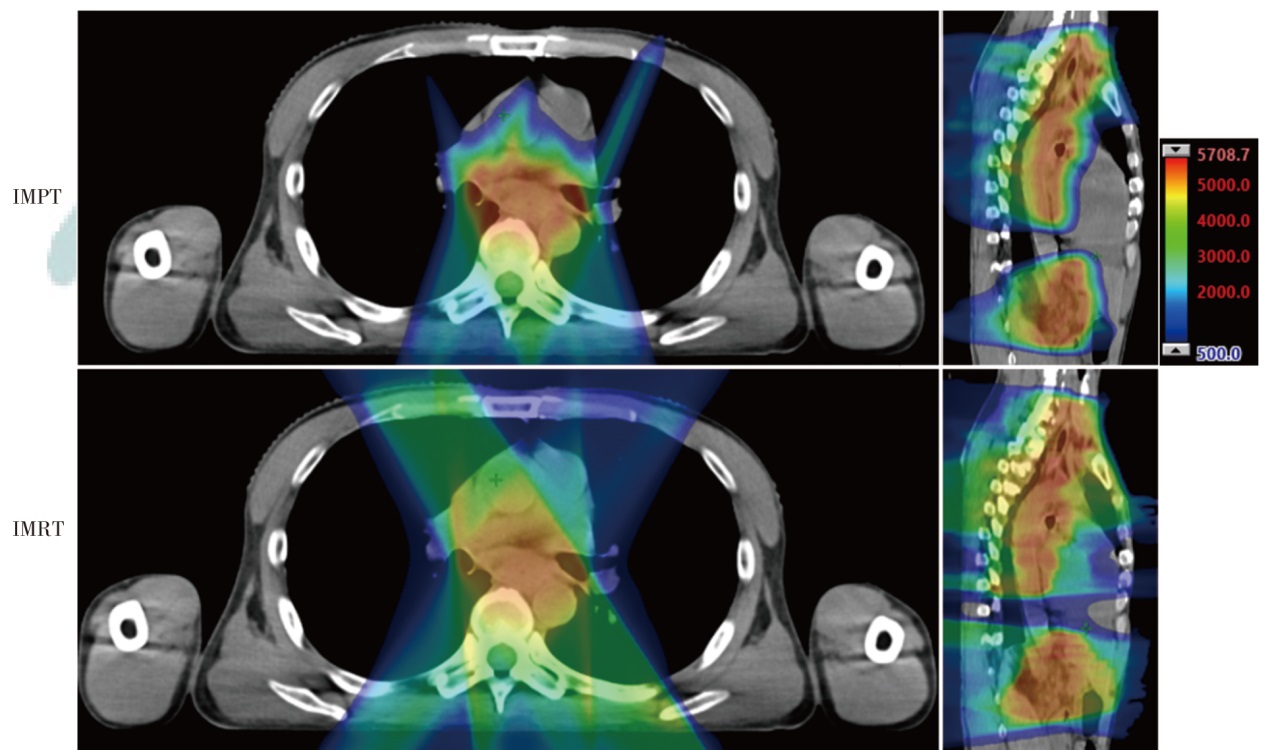

Objective To explore the dosimetric characteristics of proton radiotherapy plan and photon radiotherapy plan for esophageal cancer. Methods Four patients who were admitted to Shandong Cancer Hospital and Institute from January 2024 to April 2024 with esophageal cancer (cervical, middle thoracic and total esophageal tube, as well as the lymphatic drainage areas involved) and required radiotherapy were selected as the research subjects. Intensity modulated proton therapy (IMPT) and intensity modulated radiation therapy (IMRT) plans were designed respectively based on the clinical target volume and the dose constraints for organs at risk (OARs). Dosimetric parameters, including conformity index (CI), homogeneity index (HI), gradient index (GI) for target coverage, as well as OARs dosimetric parameters were evaluated. The volume of additional dose deposition in the body was compared by assessing regions receiving 10%, 30%, and 50% of the prescription dose. Results For all four cases, IMPT plans yielded lower HI values (0.12, 0.10, 0.06, and 0.08) than IMRT plans (0.15, 0.13, 0.10, and 0.11), and the GI values of IMPT plans (3.11, 3.21, 2.43, and 2.72) was lower than IMRT plans (4.52, 5.14, 3.09, and 3.92). Moreover, the CI of the IMPT plans (0.59, 0.60, 0.77, and 0.72) was inferior to IMRT plans (0.81, 0.77, 0.91, and 0.85). Compared with the IMRT plans, in the whole lung dose indicators of the IMPT plans for the 4 patients, V5 decreased by 34.1%, 55.0%, 79.7% and 60.3%, respectively; V20 decreased by 48.3%, 43.9%, 65.8% and 40.8%, respectively, and Dmean decreased by 43.4%, 57.2%, 76.2% and 45.4%, respectively. V30 of the heart decreased by 36.2%, 45.3%, 40.1% and 52.4%, respectively, and Dmean of heart decreased by 96.6%, 57.9%, 58.5% and 55.3%, respectively. For the middle and lower thoracic target area, the liver was significantly protected in the IMPT plan (Dmean decreased by 76.0% compared with the IMRT plan). In terms of the additional dose deposition in the patient's body, IMPT plans reduced the volumes receiving 10%, 30% and 50% of the prescription dose by 45.0%-61.4%, 41.2%- 61.8% and 34.8%-61.6%, respectively, compared with the IMRT plans. Conclusions By comparing the dosimetric parameters of IMPT and IMRT plans for 4 cases of esophageal cancer, the IMPT plans have advantages in reducing the doses to lung tissue, heart, and liver, and can also reduce additional dose deposition in the patient's body.